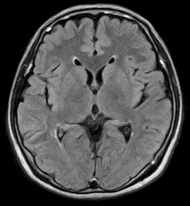

脳ドックで評価できるのは、無症候性脳梗塞(かくれ脳梗塞)、未破裂脳動脈瘤、脳腫瘍、そして認知症です。MRIやエコーに加えて、血液検査、心電図、神経学的診察では、動脈硬化や脳卒中を起こしうる不整脈(心房細動)、パーキンソン病や本態性振戦の有無が評価できます。

頭部MRI・頭部MRA・頚部MRA